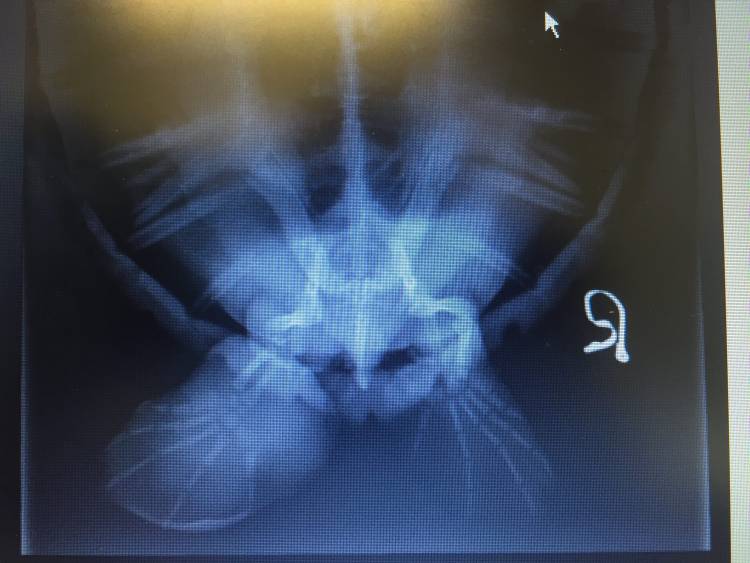

A postmortem examination was conducted on Marcel the turtle, to determine the cause of death, and it was found that his gut was already necrotic - the infection had already spread from his flipper and the damage was too extensive for this turtle to ever recover.

This autopsy also revealed another sad problem - Marcel's stomach contained 67 pieces of plastic - bits of hard microplastic, pieces of rope, clothing fibres and plastic shopping bag fragments. Although ingested plastic was not the cause of death in the case of Marcel, the sheer quantity of plastic we found was alarming. These must have been fragments of plastic that he had consumed along the South African coastline before becoming entangled in the ghost fishing net.